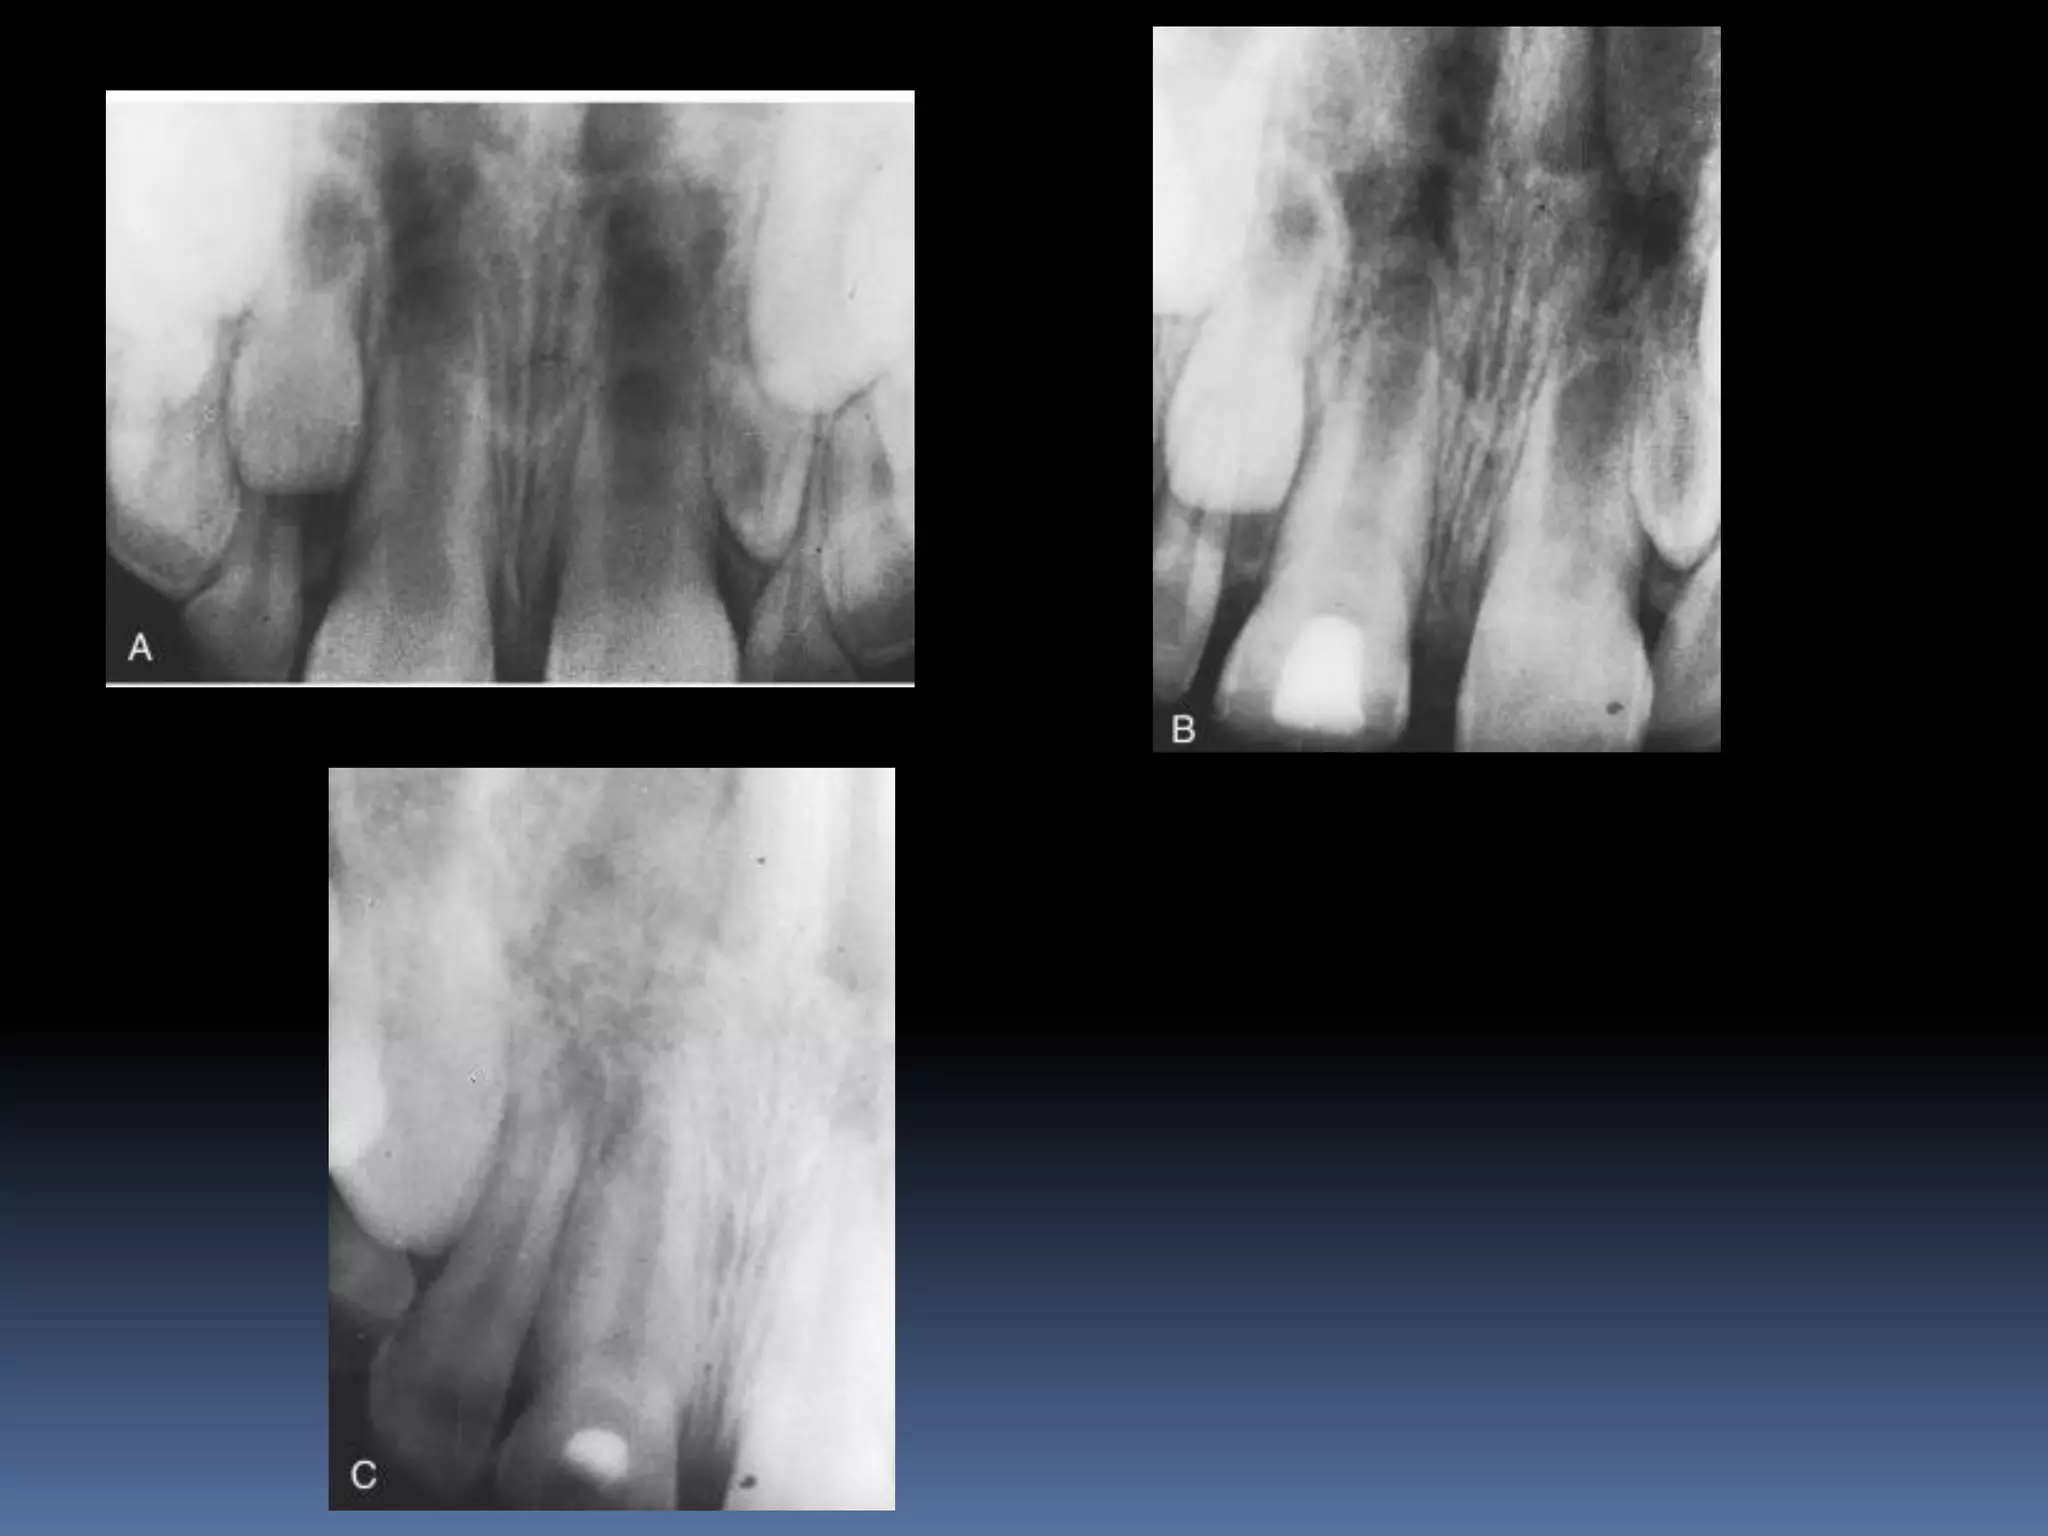

OPEN APEX  Anopen apex is the developing root of an immature tooth until apical closure occurs .  Apical closure occurs 2-3 yrs after tooth eruption  Any injury to the pulp at this stage will stop the closure of the apex  Such a tooth will have short , thin walls at the apical portion of the root

• 32.

 Open apexcan also be caused by extensive resorption of a previously mature apex after orthodontic treatment or severe periapical inflammation

Diagnosis and assessment: History  Subjective symptoms  Diagnostic tests  Radio graphs A radiolucent area usually surrounds the apex of an immature root with a healthy pulp

• 34.

OPEN APEX VITAL PULP APEXOGENESIS NONVITAL PULP APEXIFICATION

APEXOGENESIS A Vital Pulp Therapyprocedure performed to encourage continued physiologic development and formation of the root end. Since the main objective is to maintain the vitality of the radicular pulp the pulp must be vital and capable of repair